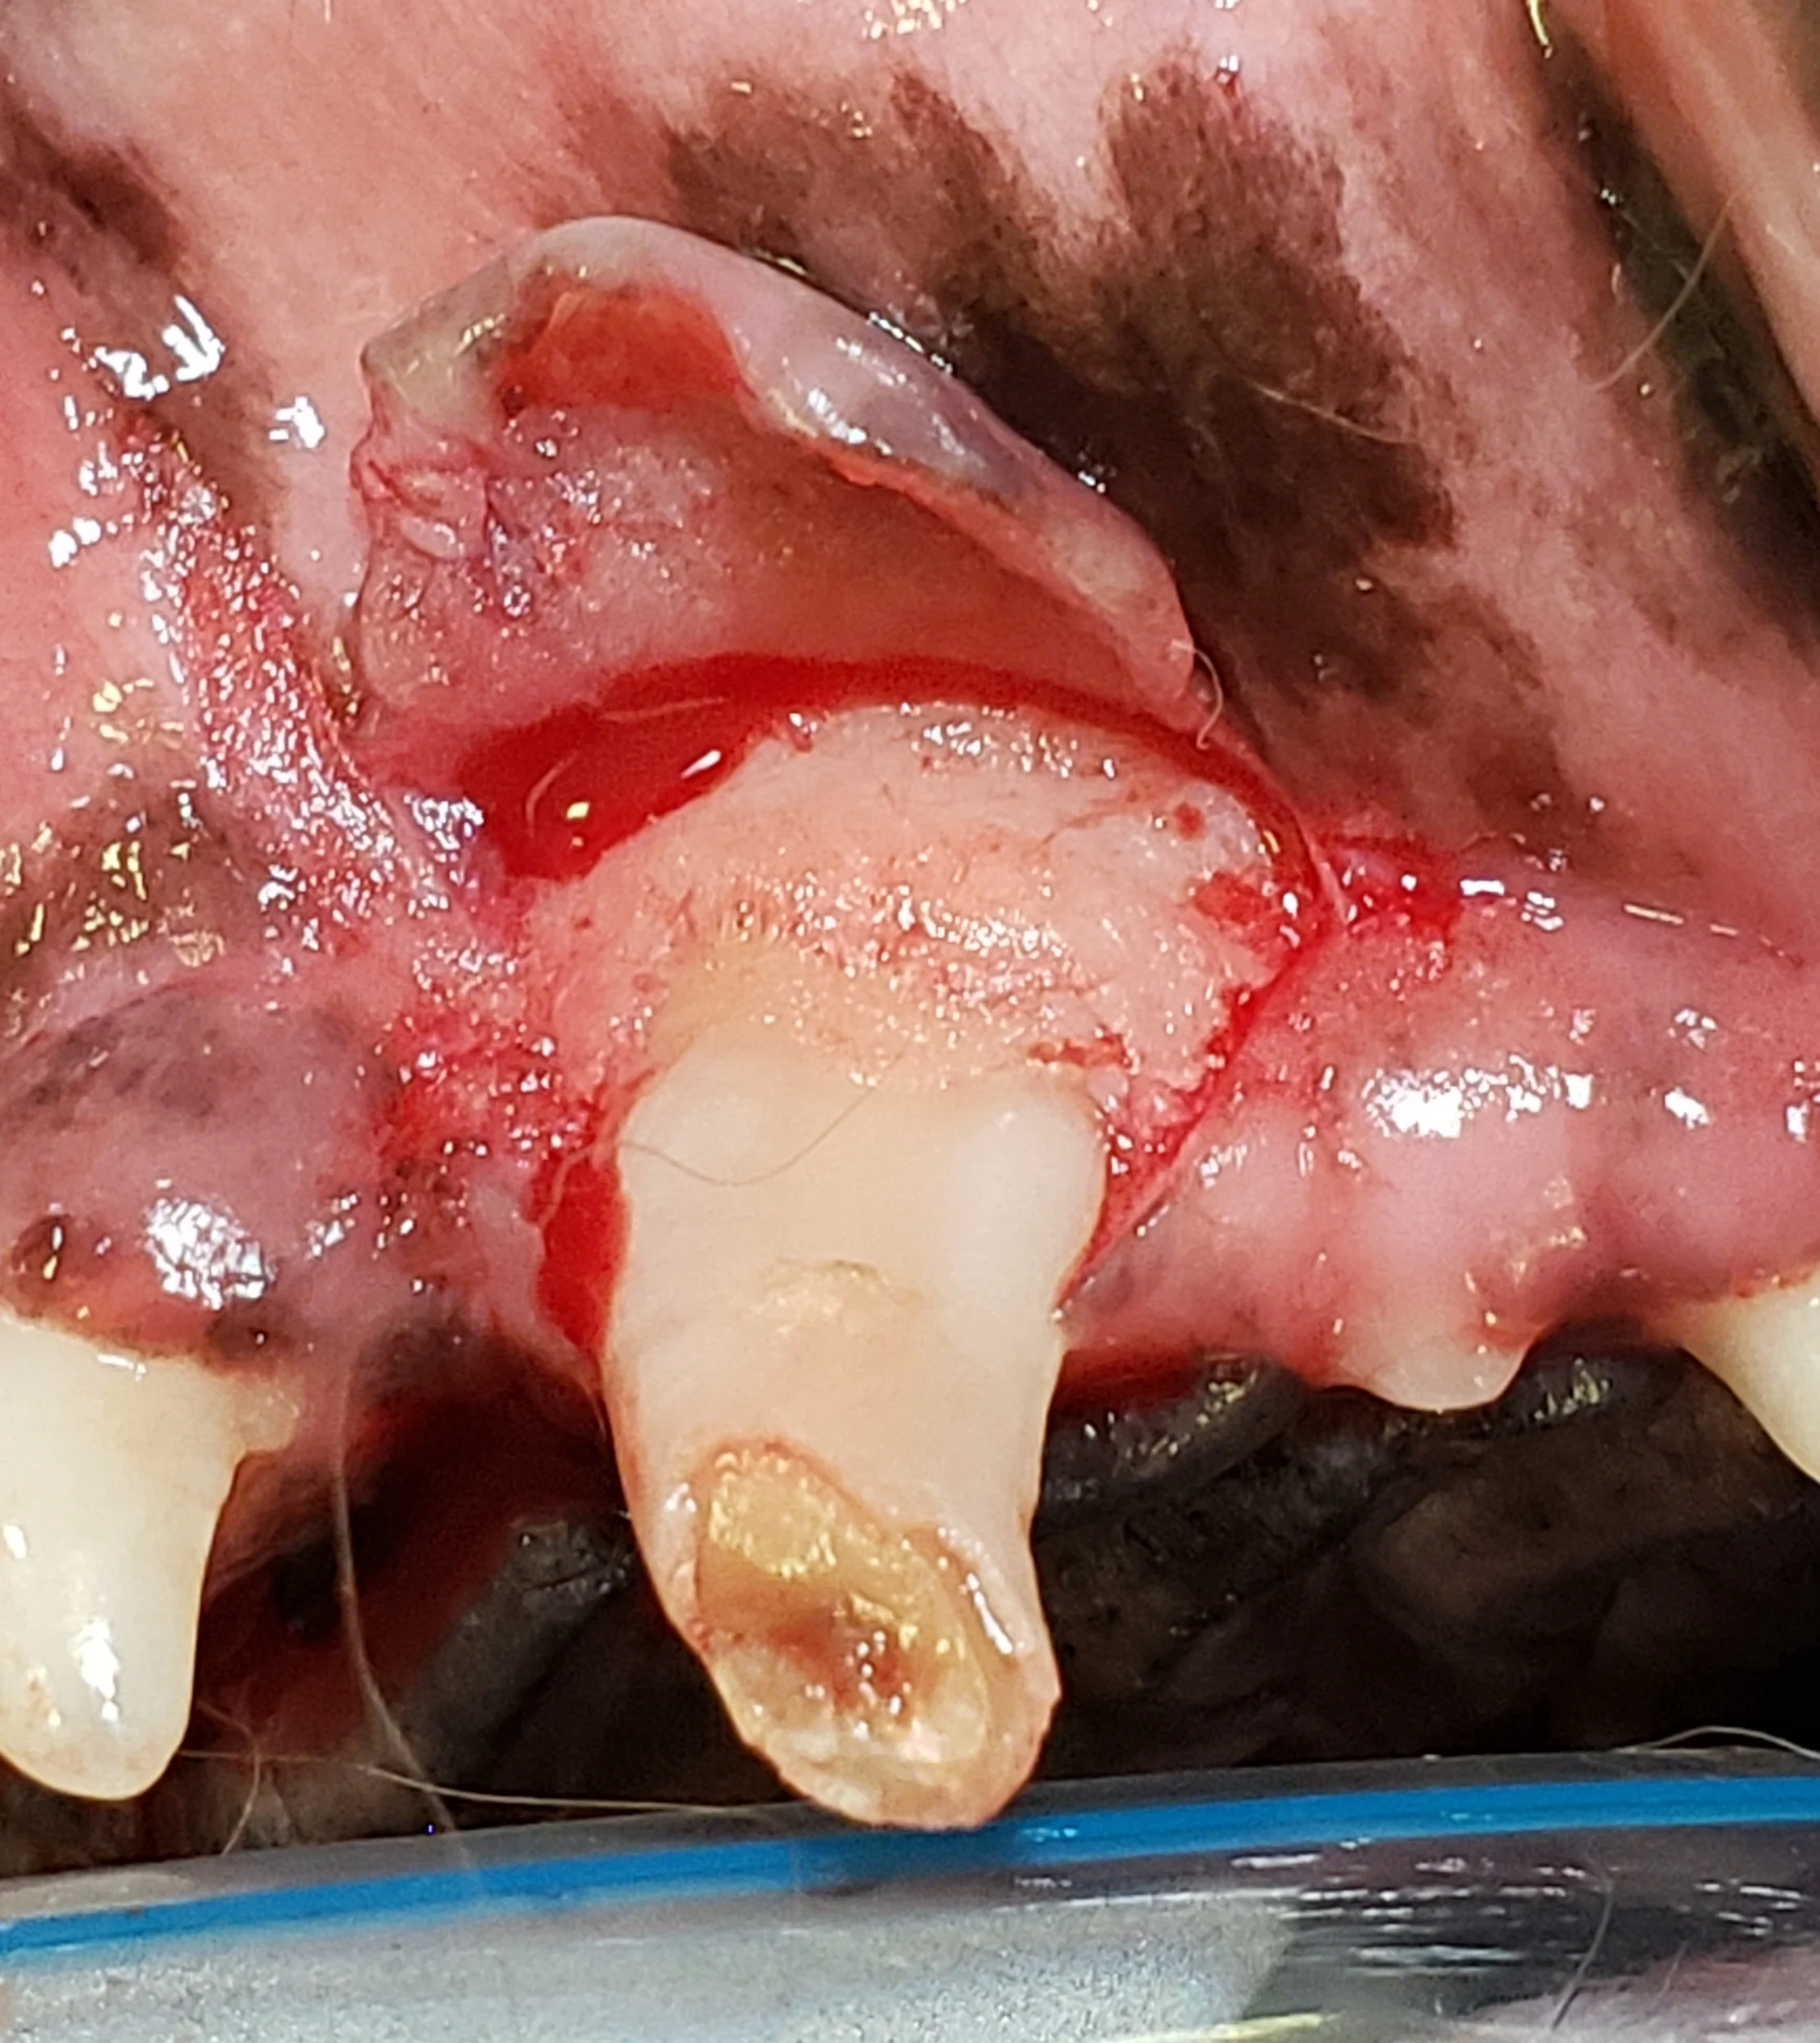

Step 5: Alveolar Bone Removal

Use a round, pear-shaped, or crosscut fissure bur to create grooves at the mesial and distal aspect of the root, at least to the level of the widest part of the root.

Author Insight

Bone removal is performed to provide adequate exposure, form an exaggerated periodontal ligament space following the root contours, and provide an opening for easier root elevation. A pear-shaped or round bur may be preferred for creating these grooves in the periodontal ligament space, as a crosscut bur can be too aggressive if used incorrectly.

Making a cut in the bone at the widest part of the root can help delineate the area in which buccal bone can be removed. A coarse diamond-cut bur is sometimes preferred to remove this buccal bone.